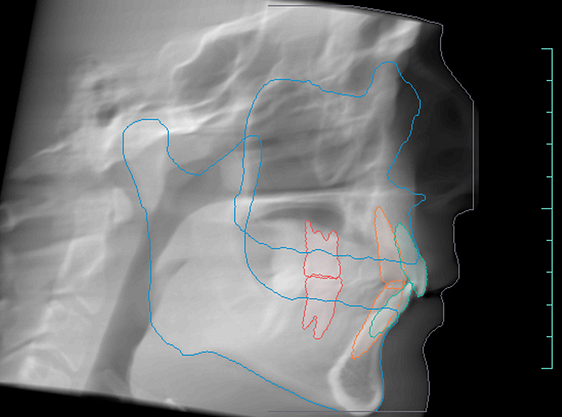

Orthodontic Report

Diagnocat is also capable of generating orthodontic reports.

This requires a CBCT radiograph with a minimum field of view of 13 x 15 x 15cm. Our Kavo OP3D machine achieves this by taking a double-field exposure and stacking two exposures on top of each other.

Diagnocat generates OPG and frontal and lateral cephalometric reconstructions from the CBCT data.

Tracings of the maxilla, mandible, central incisors, canines and molars. All automatically.

Cross-sectional and coronal views of teeth show torque and buccolingual relationships such as crossbite.

TMJ coronal/sagittal slices and summations visualize abnormal positioning/shape of the mandibular condyle.

The orthodontic report generates OPG and front/lateral cephalograms. These are not as sharp as true OPG and cephalograms. Tracings of the maxilla, mandible, central incisors, canines, and molars are automatically produced on the generated frontal/lateral cephalogram.

I showed the orthodontic report to an orthodontist colleague. She found the tracings to be fairly accurate compared to a real lateral cephalogram of the same patient. She did further tracings on the generated lateral ceph and advised it was difficult to visualize points such as Nasion, ANS, A Point, Condylion, and Orbitae and visualize the fourth vertebrae to determine peak growth phase. Furthermore, other orthodontic software can automatically calculate skeletal/dental relationships, planes, and angles.

The company did inform us that they are working on full functionality sets for orthodontic reports. This will come next year.